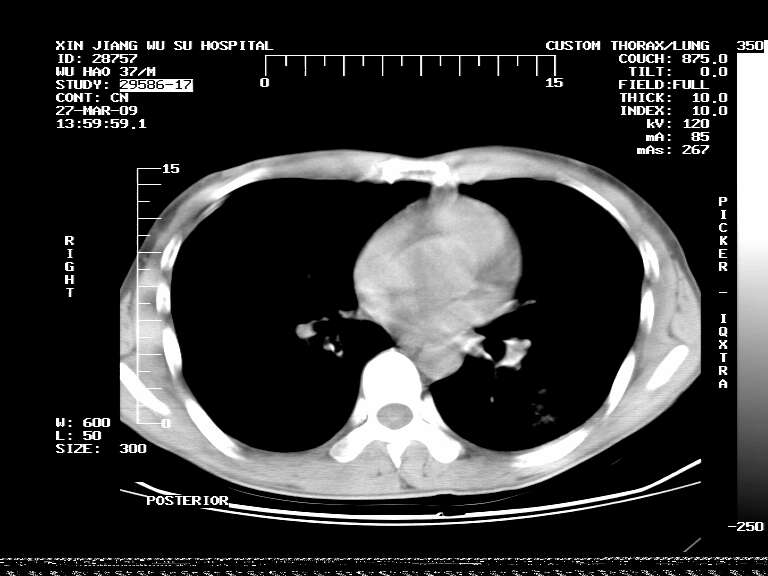

男,37岁,体检胸透发现阴影。

患者体检发现 无症状 左肺下叶占位,边缘模糊,可见血管聚束、分叶、胸膜牵拉,增强呈不均匀性强化。 首先考虑左肺下叶周围型肺癌,建议穿刺活检。

左肺下叶见一结节病变,边缘欠清不光滑,与胸膜粘连且胸膜局限性增厚,注药后呈环形强化,动脉期壁呈明显点环状强化,静脉期壁强化减低,中心密度低无强化,灶周无明显的卫星灶和水肿区(晕征)---考虑周围性肺癌,不除外感染性病变,建议穿刺活检。

左肺下叶软组织病灶,密度较高,内见点状钙化,其周围见子灶,邻近胸膜扁平样增厚.c+病灶强化明显,中心强化弱.诊断:左肺下叶结核瘤.

周围有卫星灶,胸膜反应不明显,病灶中心有坏死。建议先抗结核治疗后,短期复查

左肺下叶大片实变影,内靠胸膜见不规则更高密度结节灶,边缘强化,相邻胸膜增厚,胸膜下脂肪线存在。考虑炎症,结核可能。